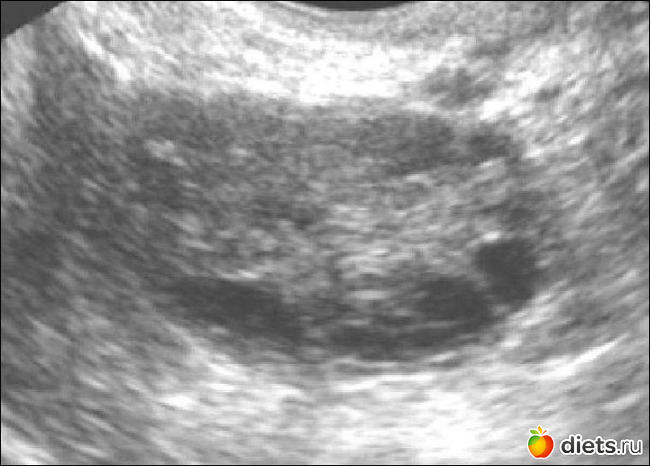

Мультифолликулярные яичники и дюфастон беременность - фото презентация